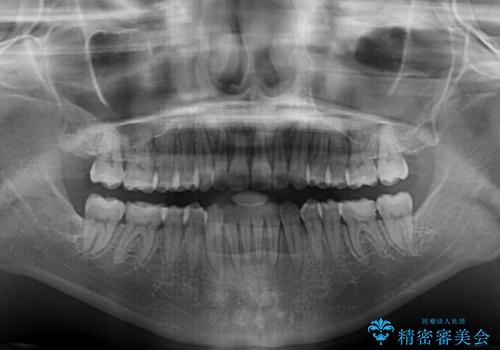

【モニター】オープンバイトをインビザラインで矯正治療

- 前歯の上下スペースによる食べにくさを気にして来院された患者様です。

インビザラインにより上下の前歯の隙間を閉じていくこととしました。

前歯のデコボコの解消と並行して上下の奥歯を圧下させるようにすることで、前歯を接触させるように計画しました。

上下の隙間に舌が入り込むことがオープンバイトの原因であったため、舌の筋肉のトレーニングも並行して行い、後戻りの抑制を図りました。